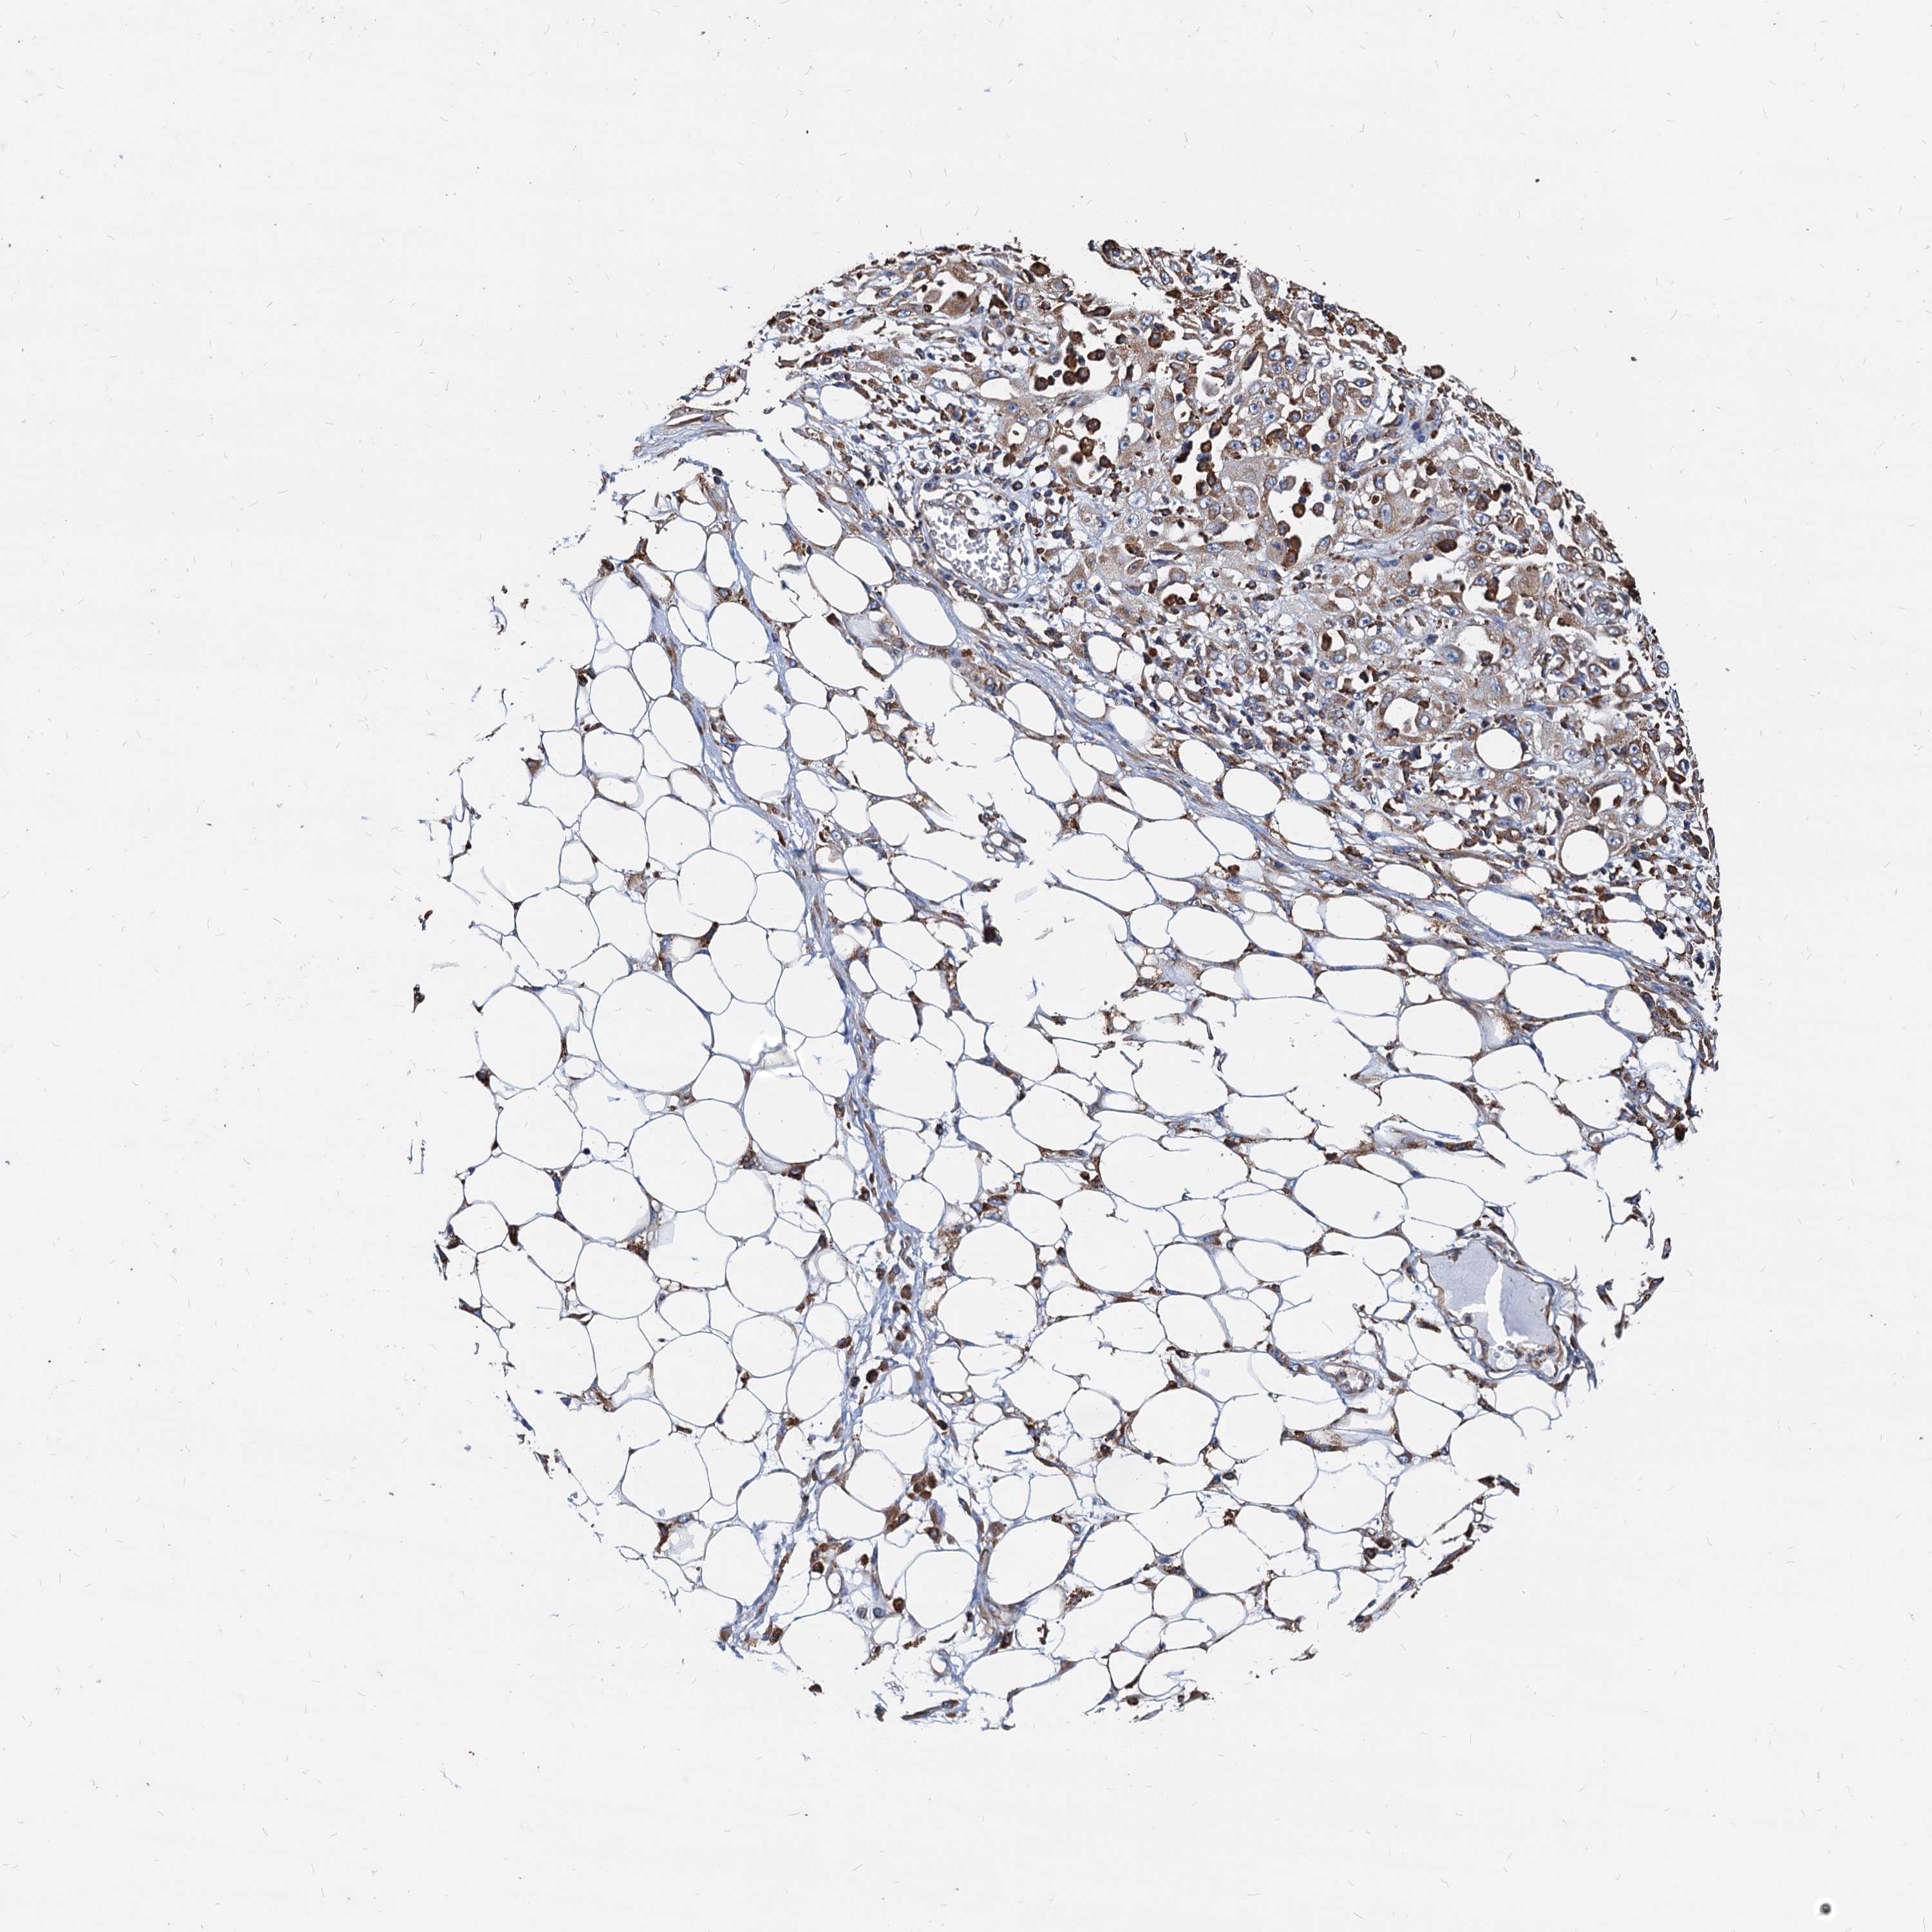

SKIN CANCER - Protein expressioni

A mouse-over function shows sample information and annotation data. Click on an image to view it in a full screen mode. Samples can be filtered based on level of antibody staining by selecting one or several of the following categories: high, medium, low and not detected. The assay and annotation is described here.

Each image is clickable and will lead to virtual microscopy that enables deeper exploration of all samples and also displays staining intensity scores, fraction scores and subcellular localization as well as patient and tissue information for each sample.

Antibody HPA038845

Staining

Medium

Moderate

75%-25%

Cytoplasmic/membranous

Squamous cell carcinoma, metastatic, NOS

Squamous cell carcinoma, NOS